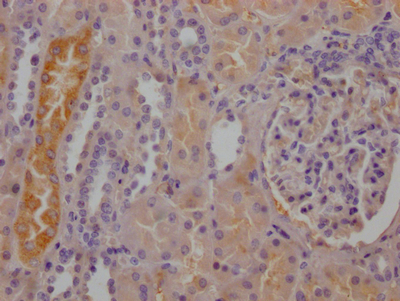

IHC image of CSB-RA784971A0HU diluted at 1:100 and staining in paraffin-embedded human kidney tissue performed on a Leica BondTM system. After dewaxing and hydration, antigen retrieval was mediated by high pressure in a citrate buffer (pH 6.0). Section was blocked with 10% normal goat serum 30min at RT. Then primary antibody (1% BSA) was incubated at 4°C overnight. The primary is detected by a Goat anti-rabbit IgG polymer labeled by HRP and visualized using 0.05% DAB.